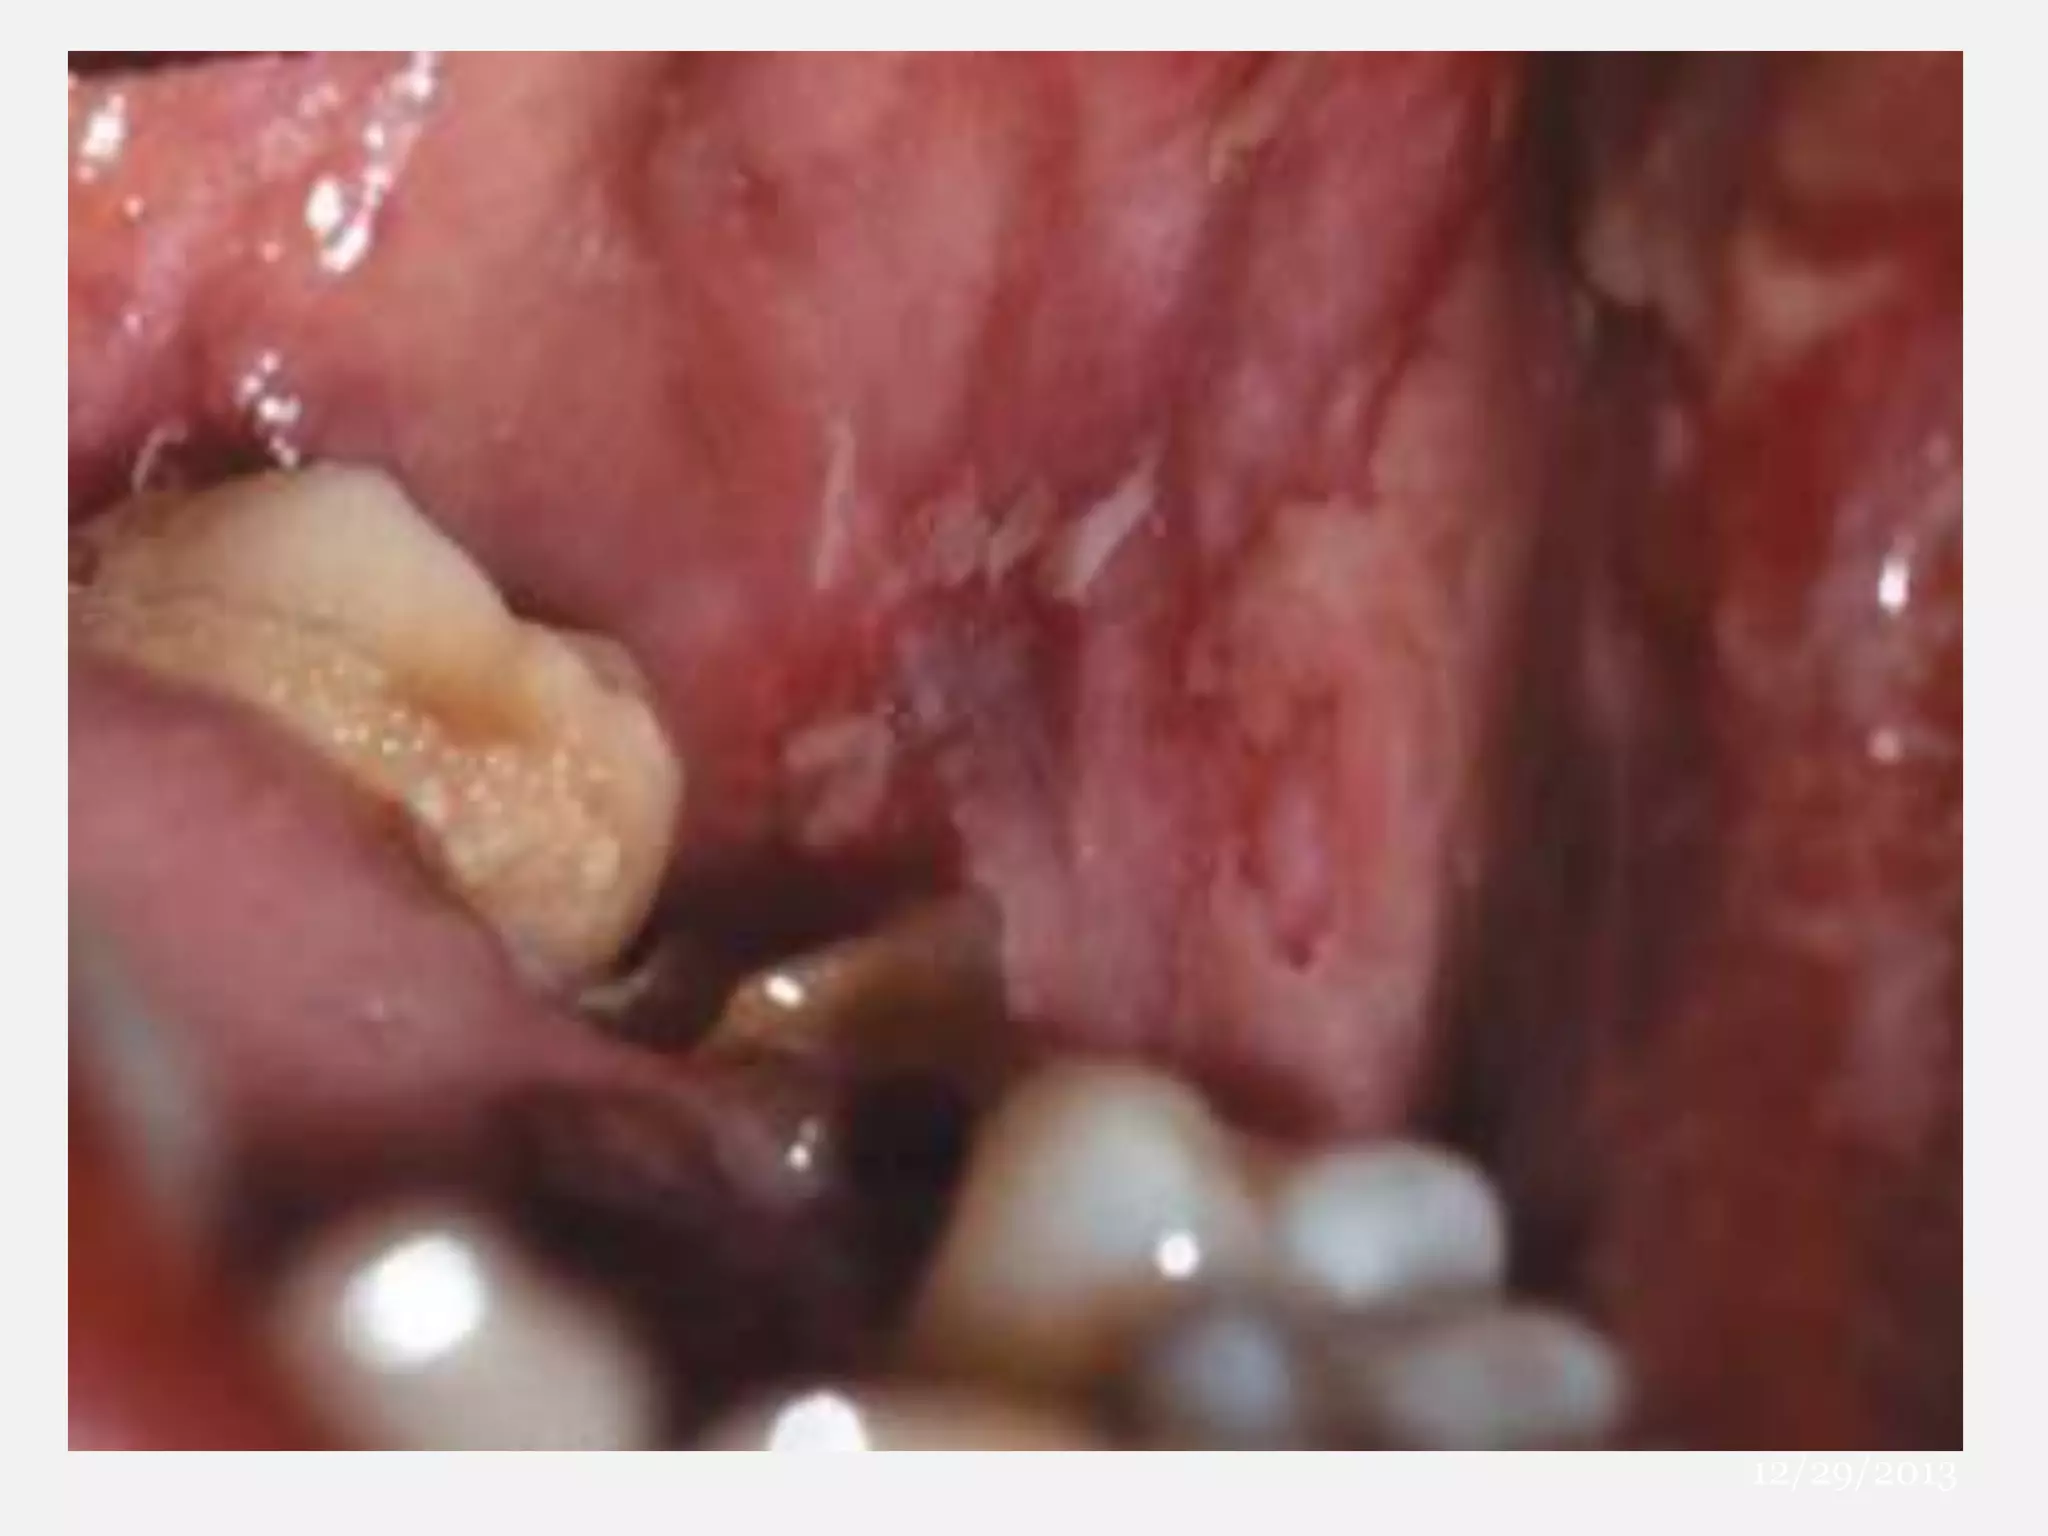

MUCOSAL LESIONS

12

 70% Cases

 Lips – Cutaneous

Target Lesions

Serous Crusting

13

 LIPS – Mucosal (Erosions / Vesicles / Bullae)

 GINGIVAL / Ventral Tongue

 Hard Palate – Spared

 Pharynx / Larynx / Trachea / Bronchi

 Conjunctivitis B/L with Vesicles / Erosions

 Nasal / Urethral / Anal Mucosae

 2/3 Mucosal Sites sans Cutaneous inv

– FUCH’s SYNDROME